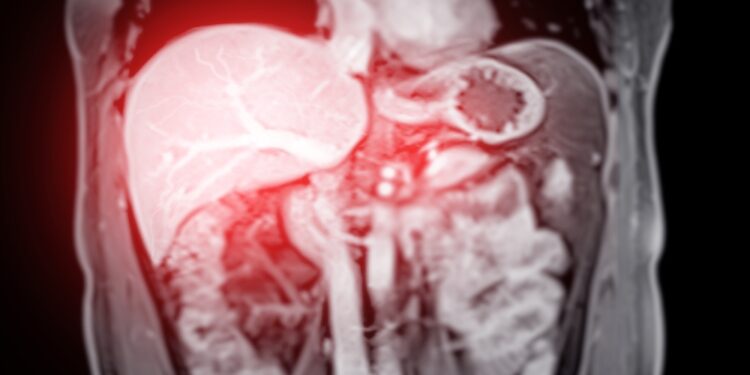

- Magnetinio rezonanso tomografija (MRT) – ypač tiksli vidaus organų vaizdinė analizė